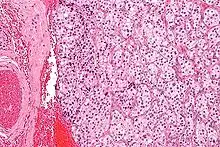

Солідна пухлина, що може бути з капсулою або частково мати капсулу. Поверхня на розрізі темно-коричнева, з вираженою васкуляризацією строми та вогнищами фіброзу. Розміри різні, часто до 5 см в найбільшому діаметрі. Мікроскопічно парагангліоми характеризується наявністю головних та сустентакулярних клітин. Головні клітини — з еозинофільною цитоплазмою та атиповими ядрами. Сустенкулярні клітини оточують головні та асоційовані з експресією протеїнів S100 та GFAP.